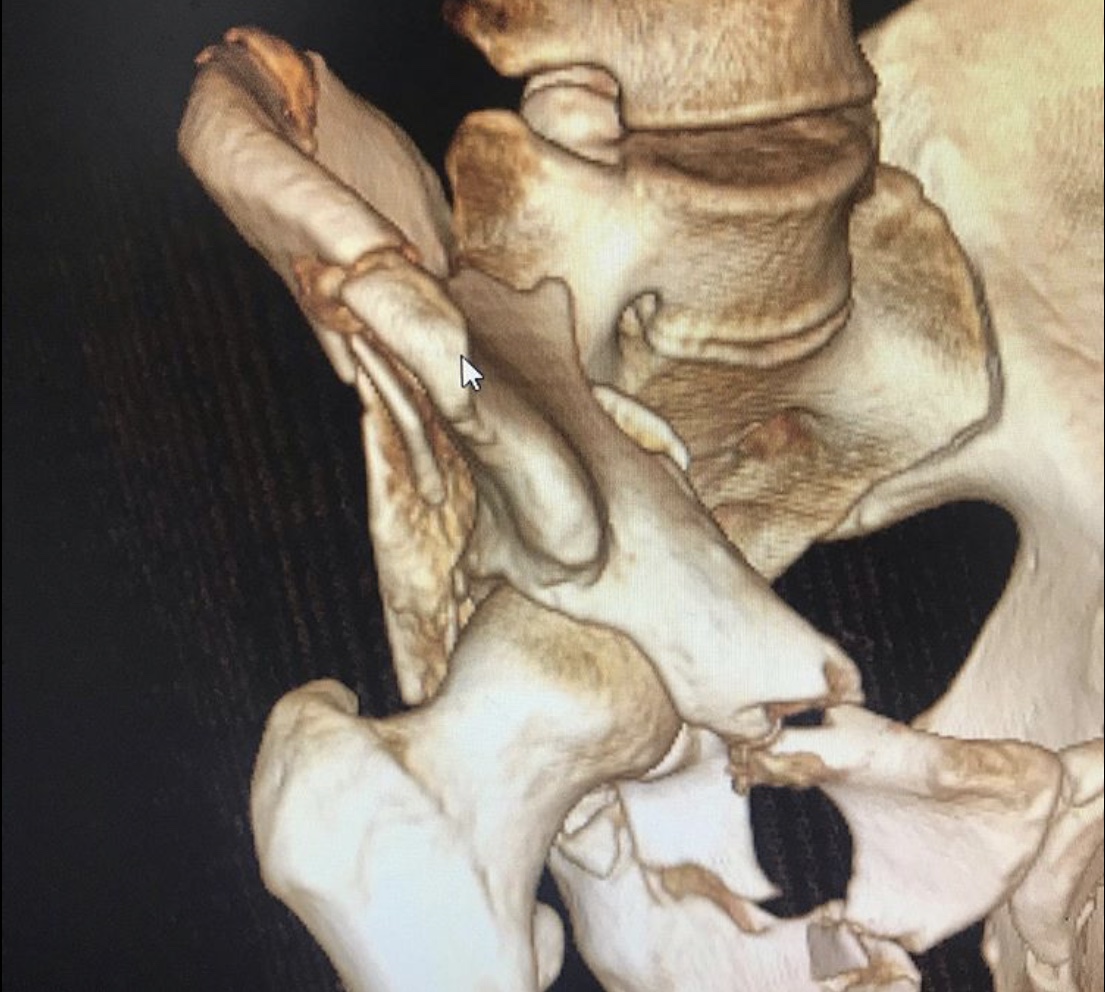

Перелом таза – тяжелейшая травма костей скелета, уступающая по опасности только травмам позвоночника и черепа. Она отличается особой опасностью, так как ее сопровождают обильная потеря крови и шока. Пострадавшему требуется экстренная врачебная помощь, иначе высок риск гибели. Даже при срочном врачебном вмешательстве не всегда удается спасти пострадавшего, который может погибнуть от кровопотери или осложнений болевого травматического шока.

Пациента, что называется, «собрали».

Была выполнена открытая репозиция, остеосинтез пластинами.